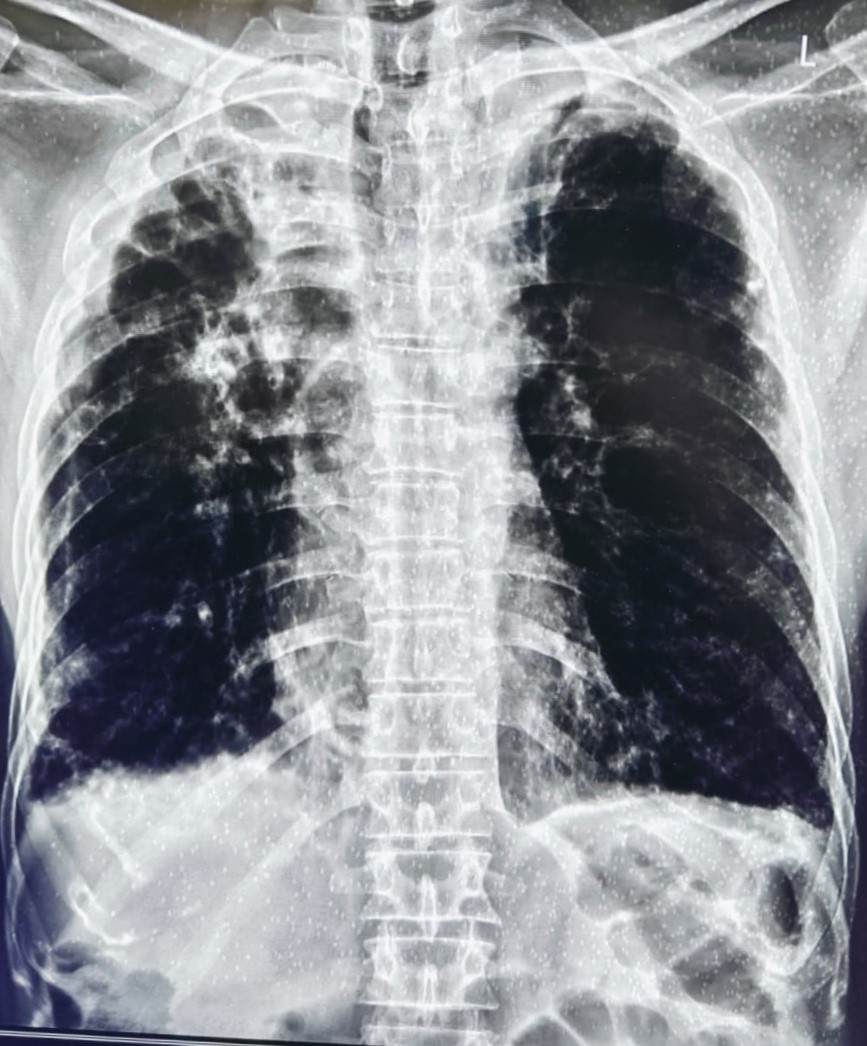

| 318 | IGGMC, Nagpur, Nagpur | P2 | 29-4154 | Tahera Bee | Consent taken on Paper | 70 Yrs. |

Provisional Diag : Post TB Bilateral Bronchiectasis

Final Diag : Post TB sequalae, Bilateral Bronchiectasis In Lower Lobe With Type 1 Respi Failure With Sepsis With Septic Shock With SYST HTN |

Post TB Sequelae | Abnormality visible on x-ray |